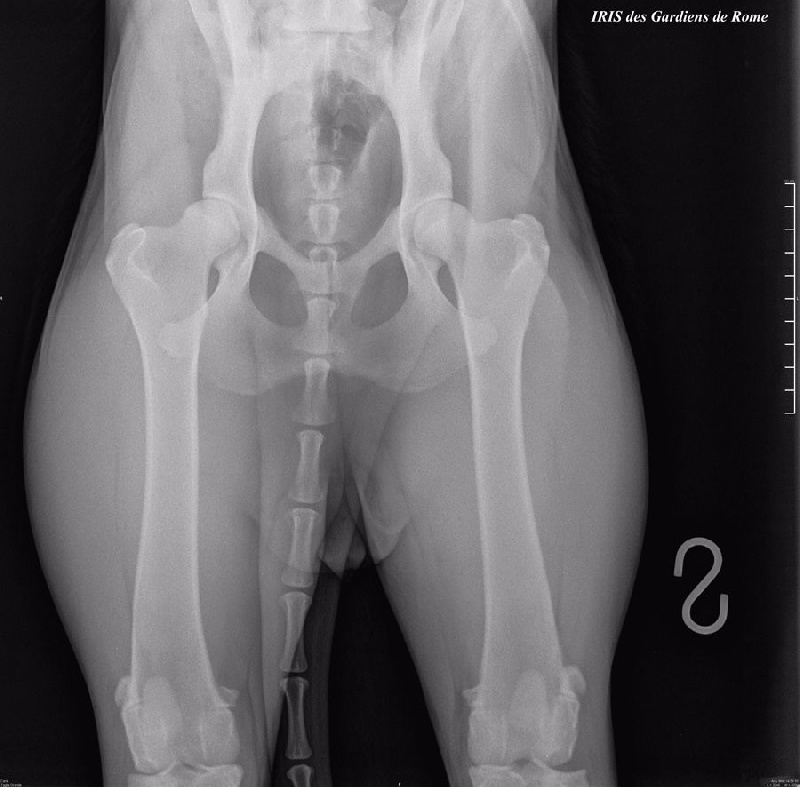

IRIS des Gardiens de Rome (radiografie anche e gomiti ufficiali)